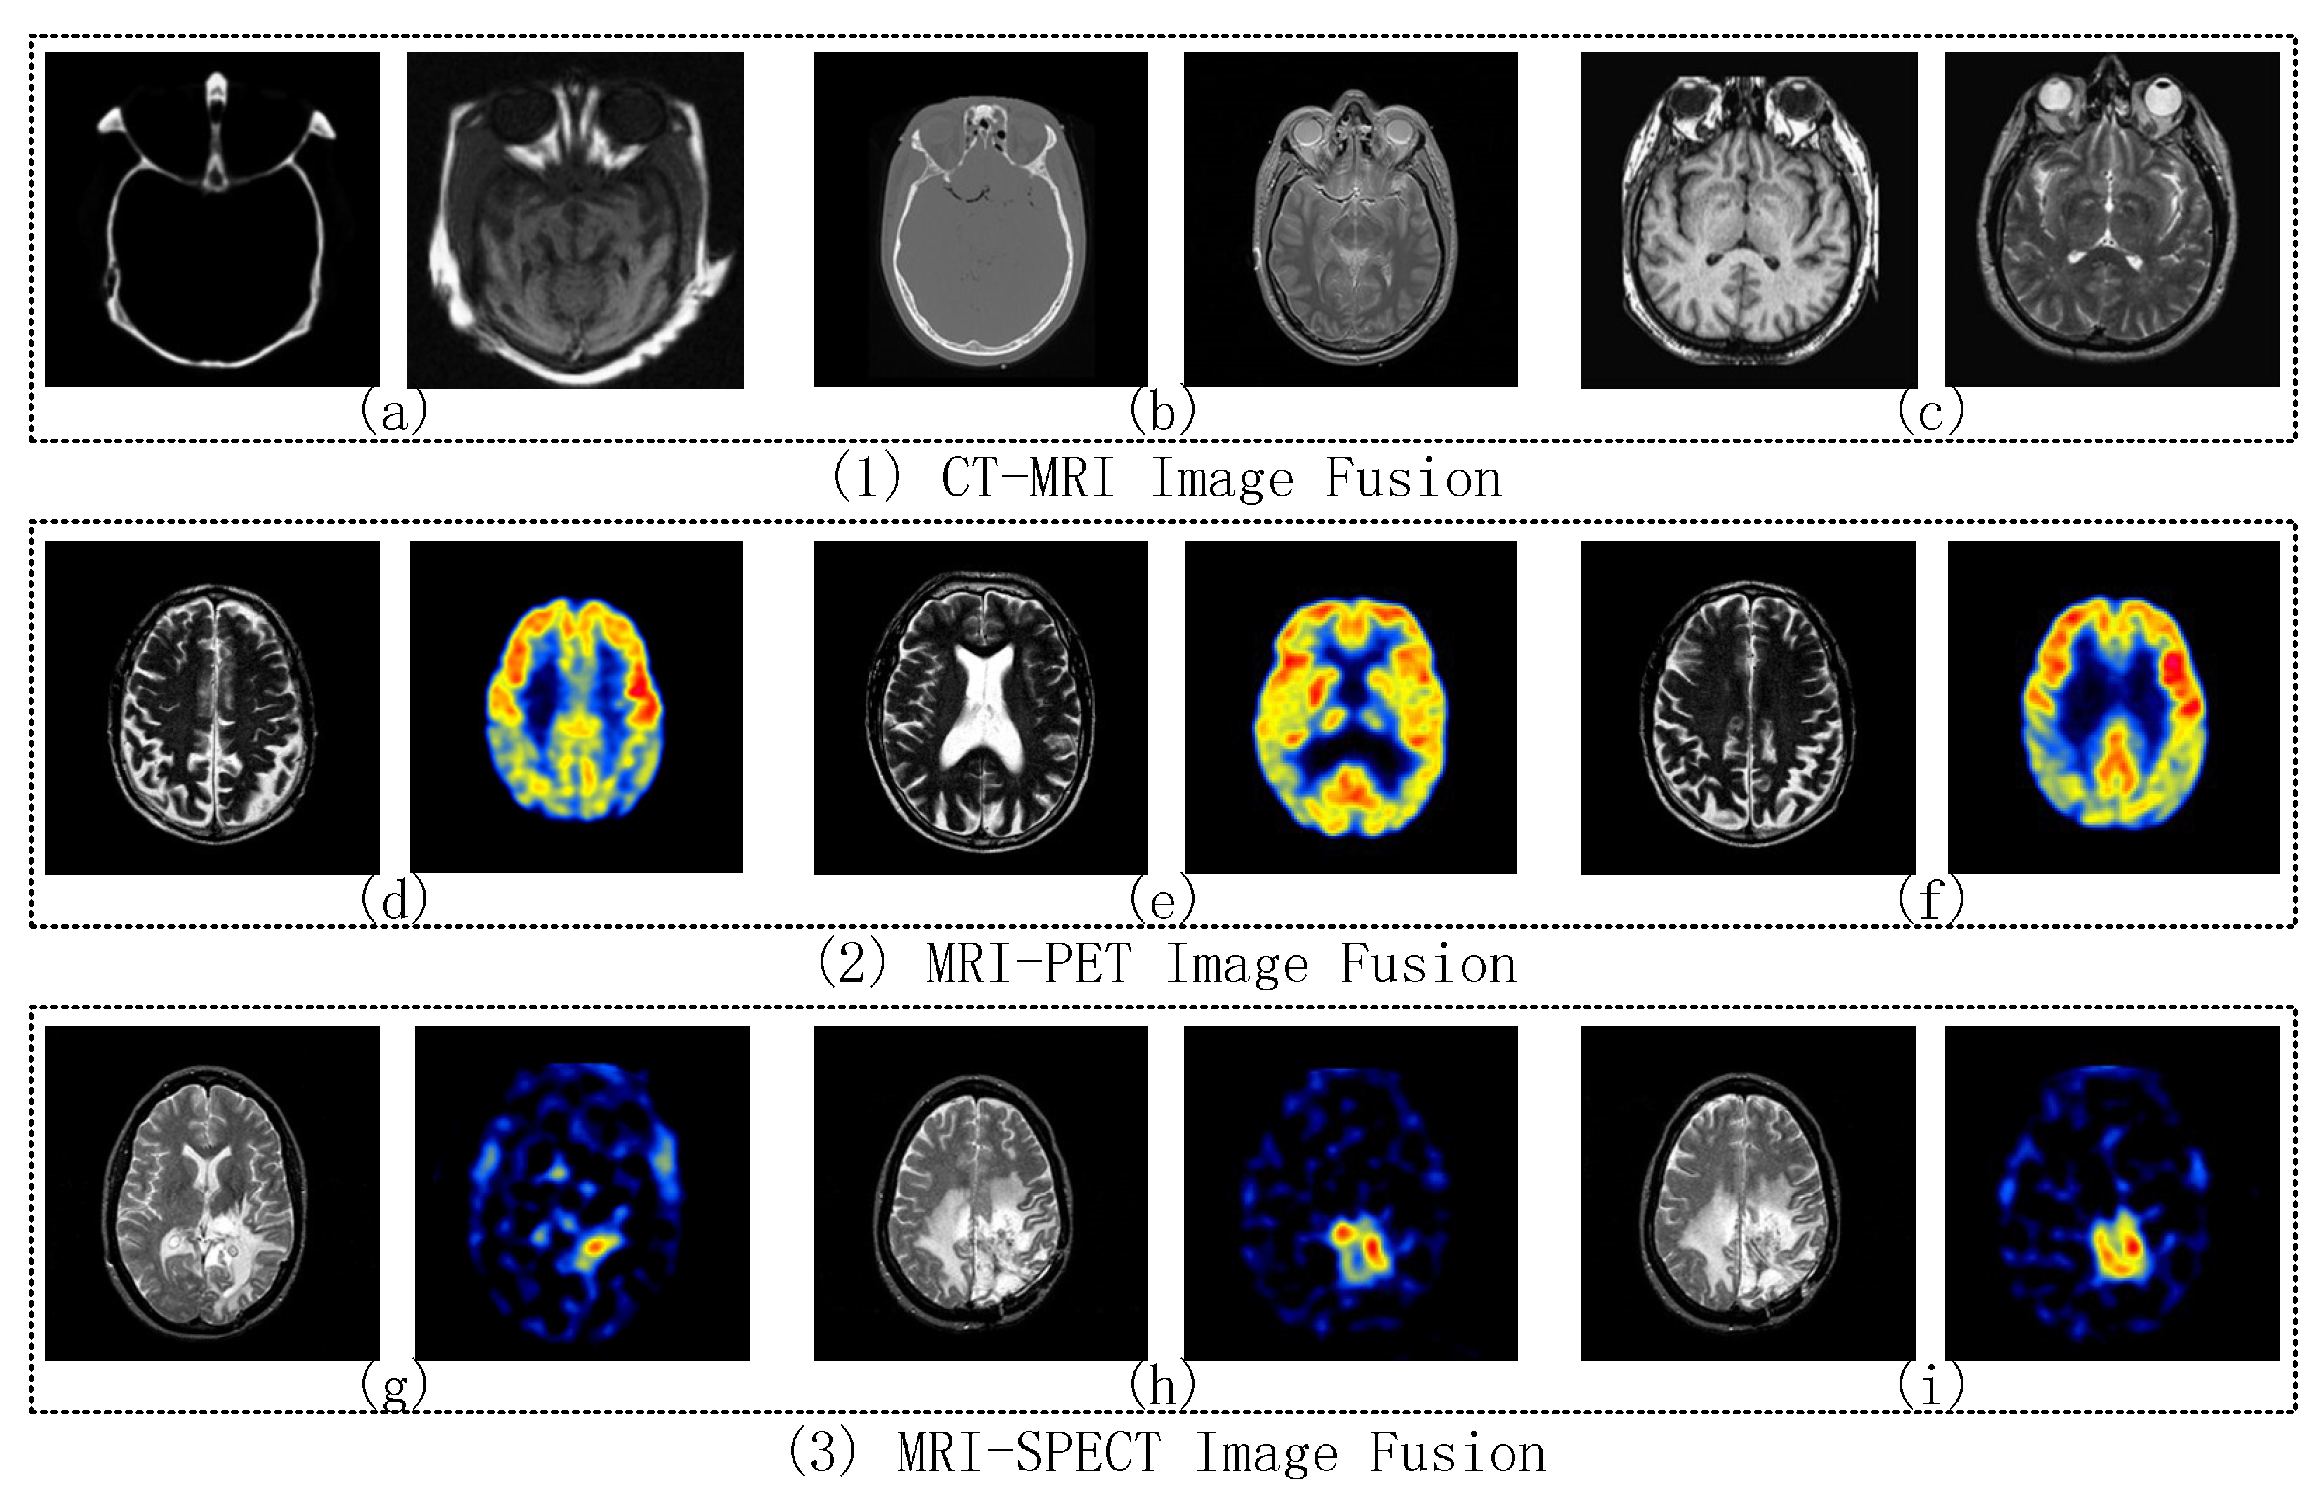

2.4. CT and MRI Images Fusion

2.5. MRI and PET Image Fusion

2.6. MRI and SPECT Image Fusion

4.2.1. CT-MRI Image Fusion Comparative Experiments

4.2.2. MRI-PET Image Fusion Comparative Experiments

4.2.3. MRI-SPECT Image Fusion Comparative Experiments